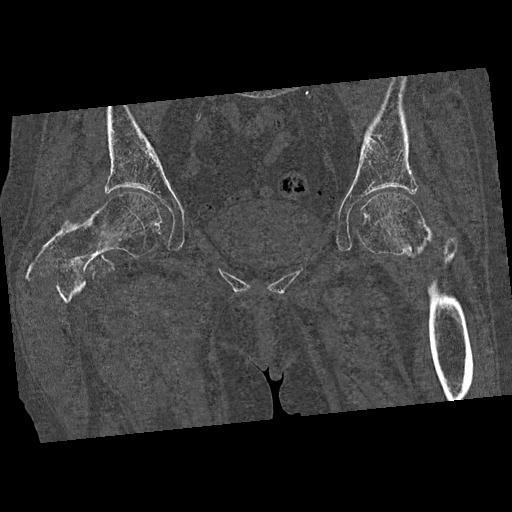

100703 1/27 両股正面+軸 1/29 両股正面+軸 94歳女性 パンソンロン

46666 1/28 両股正面+軸と 1/26 右手関節 2R 76歳女性 右転子部骨折

37 1/18 両股正面+軸 1/22 2R 86歳女性 右転子下

82084 1/14 1/20 股関節 2R 78歳男性 右人工骨頭

102811 1/13 股関節 2R 1/19 2R 80歳女性 右DHS

91569 3/25 両股正面とラウエン 70歳女性 人工骨頭+バンクーバー